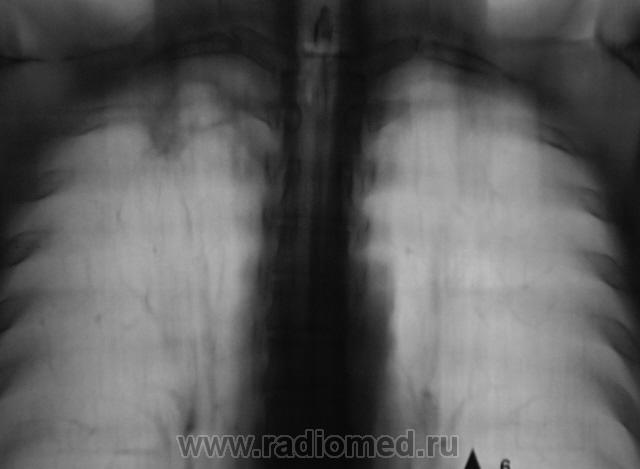

Пол пациента: Мужской пол Тип патологии: Инфекция Область исследования: Грудная клетка и верхние дыхательные пути Методы исследования: Rg При расшифровке цифровых флюорограмм пациент "взят на контроль". Смутила правая верхушка. Произведено стандартное дообследование. Ваше мнение коллеги? Пнд, 19/10/2009 - 22:26 #1 Наталия Не на сайте Был на сайте: 8 лет 7 месяцев назад Зарегистрирован: 30.07.2008 - 13:24 Публикации: 538 Полость на правой верхушке. Втр, 20/10/2009 - 07:40 #2 OPEXOB Не на сайте Был на сайте: 9 лет 11 месяцев назад Зарегистрирован: 26.07.2008 - 10:02 Публикации: 280 Ничего особенного. Повышенная пневмотизация и только. А томография 1 ребра хорошая. Втр, 20/10/2009 - 19:52 #3 Катенёв Валенти... Не на сайте Был на сайте: 7 лет 2 недели назад Зарегистрирован: 22.03.2008 - 22:15 Публикации: 54876 А что по поводу "полостного образования" мкажите коллега? Втр, 20/10/2009 - 20:08 #4 serega Не на сайте Был на сайте: 12 лет 4 месяцев назад Зарегистрирован: 15.10.2009 - 18:10 Публикации: 99 Прилежащая легочная ткань интактна- признаков воспаления нет, стенки плотные, полость "пуста". Быть может процесс старенький? Втр, 20/10/2009 - 20:17 #5 Глазков Игорь А... Не на сайте Был на сайте: 9 месяцев 2 недели назад Зарегистрирован: 19.12.2008 - 20:41 Публикации: 1597 похожа на туберкулёзную каверну. Прийди к Себе

Полость на правой верхушке.

Ничего особенного. Повышенная пневмотизация и только. А томография 1 ребра хорошая.

Прилежащая легочная ткань интактна- признаков воспаления нет, стенки плотные, полость "пуста". Быть может процесс старенький?

похожа на туберкулёзную каверну.